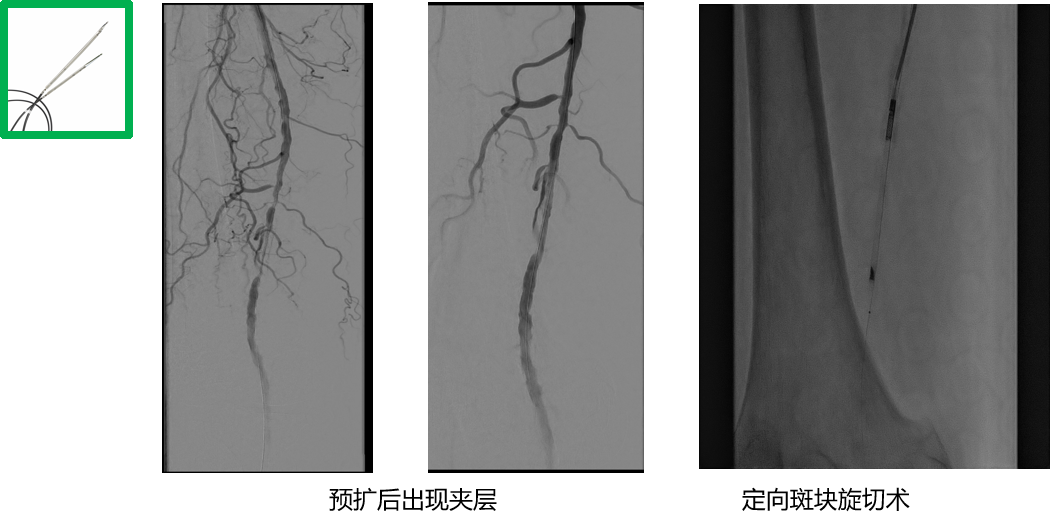

严重的钙化斑块——定向斑块旋切术

针对严重钙化斑块,可预扩后使用Hawk进行减容

病变类型:严重钙化、长病变

导丝选择:

V-18

Victory™-18,

Asahi Treasure™ 12,

Asahi Astato™ 20,

Asahi Astato™ 30

预扩球囊:

Bantam™ 2x120mm balloon